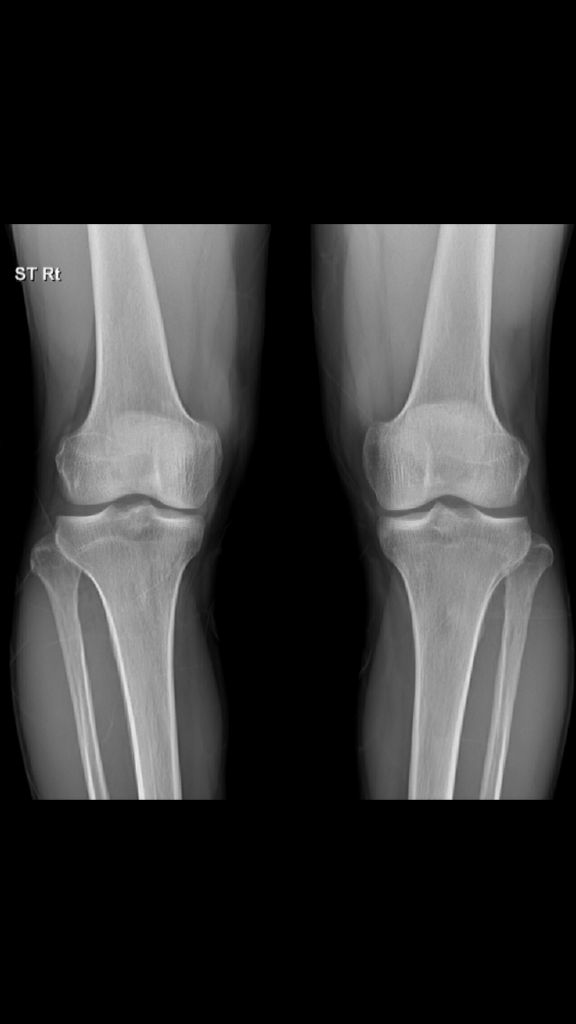

무릎관절 엑스레이 한번봐주세요

무릎이 아픕니다 왼쪽이더요

엑스레이상 안쪽이 쫌 낮은거같은데 닳아서 안쪽이 쫌 낮아진건지 원래 사람 이정도 차이는 있는건지 알수있을까요?

엑스레이 검사를 통해서는 연골이나 인대 등에 대한 구조물은 평가 가능하지 않습니다. 올리신 사진의 엑스레이 소견에는 특별히 문제가 있어 보이는 부분이 있어 보이지 않습니다. 정상적으로도 안쪽이 바깥쪽보다 다소 뼈 사이 공간이 좁을 수 있습니다.

올려주신 무릎 엑스레이를 보면 양쪽 무릎 관절 간격이 조금 차이가 나고 왼쪽 무릎 안쪽 관절 간격이 상대적으로 좁아진 것처럼 보입니다.

이는 일반적으로 내측 관절 연골이 닳아 발생하는 초기 퇴행성 변화일 가능성을 시사합니다.

사람마다 양쪽 무릎 간격이 약간 다를 수 있지만 통증이 있고 한쪽이 유독 좁아진 경우에는 퇴행성 변화 가능성을 고려해야 합니다!